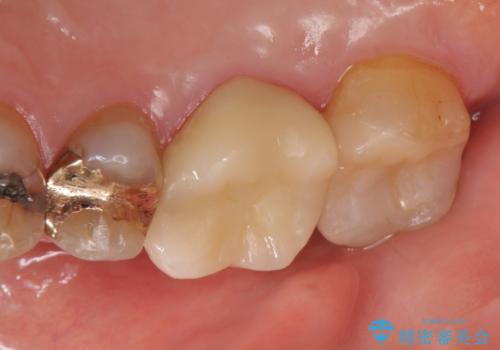

その後歯茎の回復を待ち、オールセラミッククラウンおよびセラミックインレーによる補綴・修復を行いました。

当院のセラミックインレーはemaxという強度と審美性に優れた材料を使用しています。

またプレス方式でインレーを製作しているため、削り出しで製作するCADCAMより優れた適合性も持ち合わせており、虫歯が再発しにくい修復物です。

今回用いたオールセラミッククラウンはジルコニアフレームという白い素材の上にセラミックを盛っているため、審美性が非常に高いのが特徴です。

また、ジルコニアは人工ダイヤモンドの材料にも使われているほど高い強度を持っており、そのためオールセラミッククラウンは審美性だけでなく、奥歯やブリッジの補綴も可能とするクラウンです。